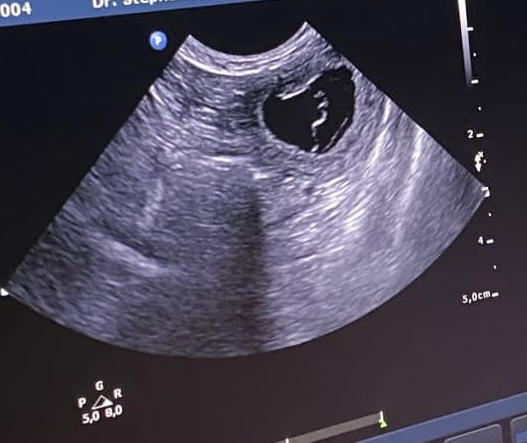

26.07.2023

Es hat geklappt!

Edda hat aufgenommen und erwartet Nachwuchs.

Jetzt heißt es erst einmal pflegen und brüten.

Wir freuen uns auf Ende August. Dann kommen die Welpen!